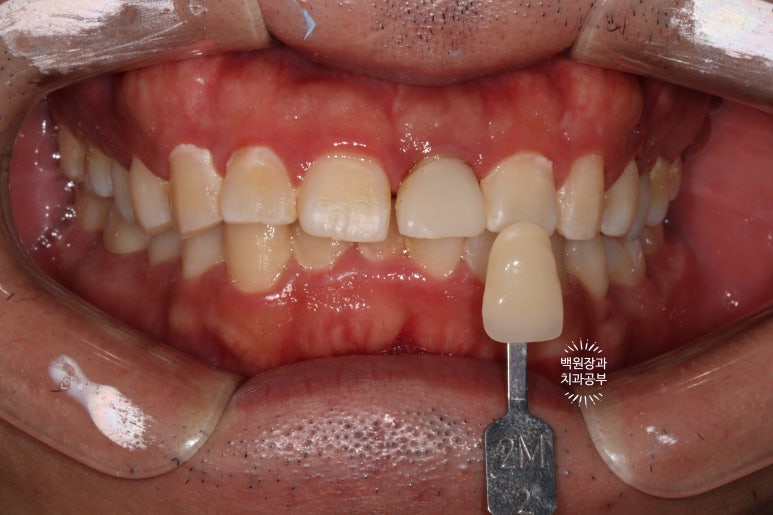

인상채득을 하고, 치아색을 선택합니다.

임플란트 1차 수술 후 3달이 지나면 인상채득을 시행합니다.

흔히 말하는 뽄뜨는 날이죠!!

가장 중요한 것은 색상 대조표 (shade guide)를 사용하여 주변 치아와 비슷한 색상을 찾는 것입니다.

VITA shade guide 2M2로 제작하기로 하였습니다.

그리고 구강위생관리의 부족으로 다시 치태가 쌓이기 시작해서 치석제거를 한 번 더 시행하였습니다.